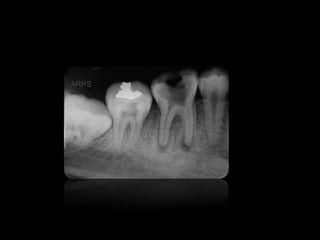

CARIES